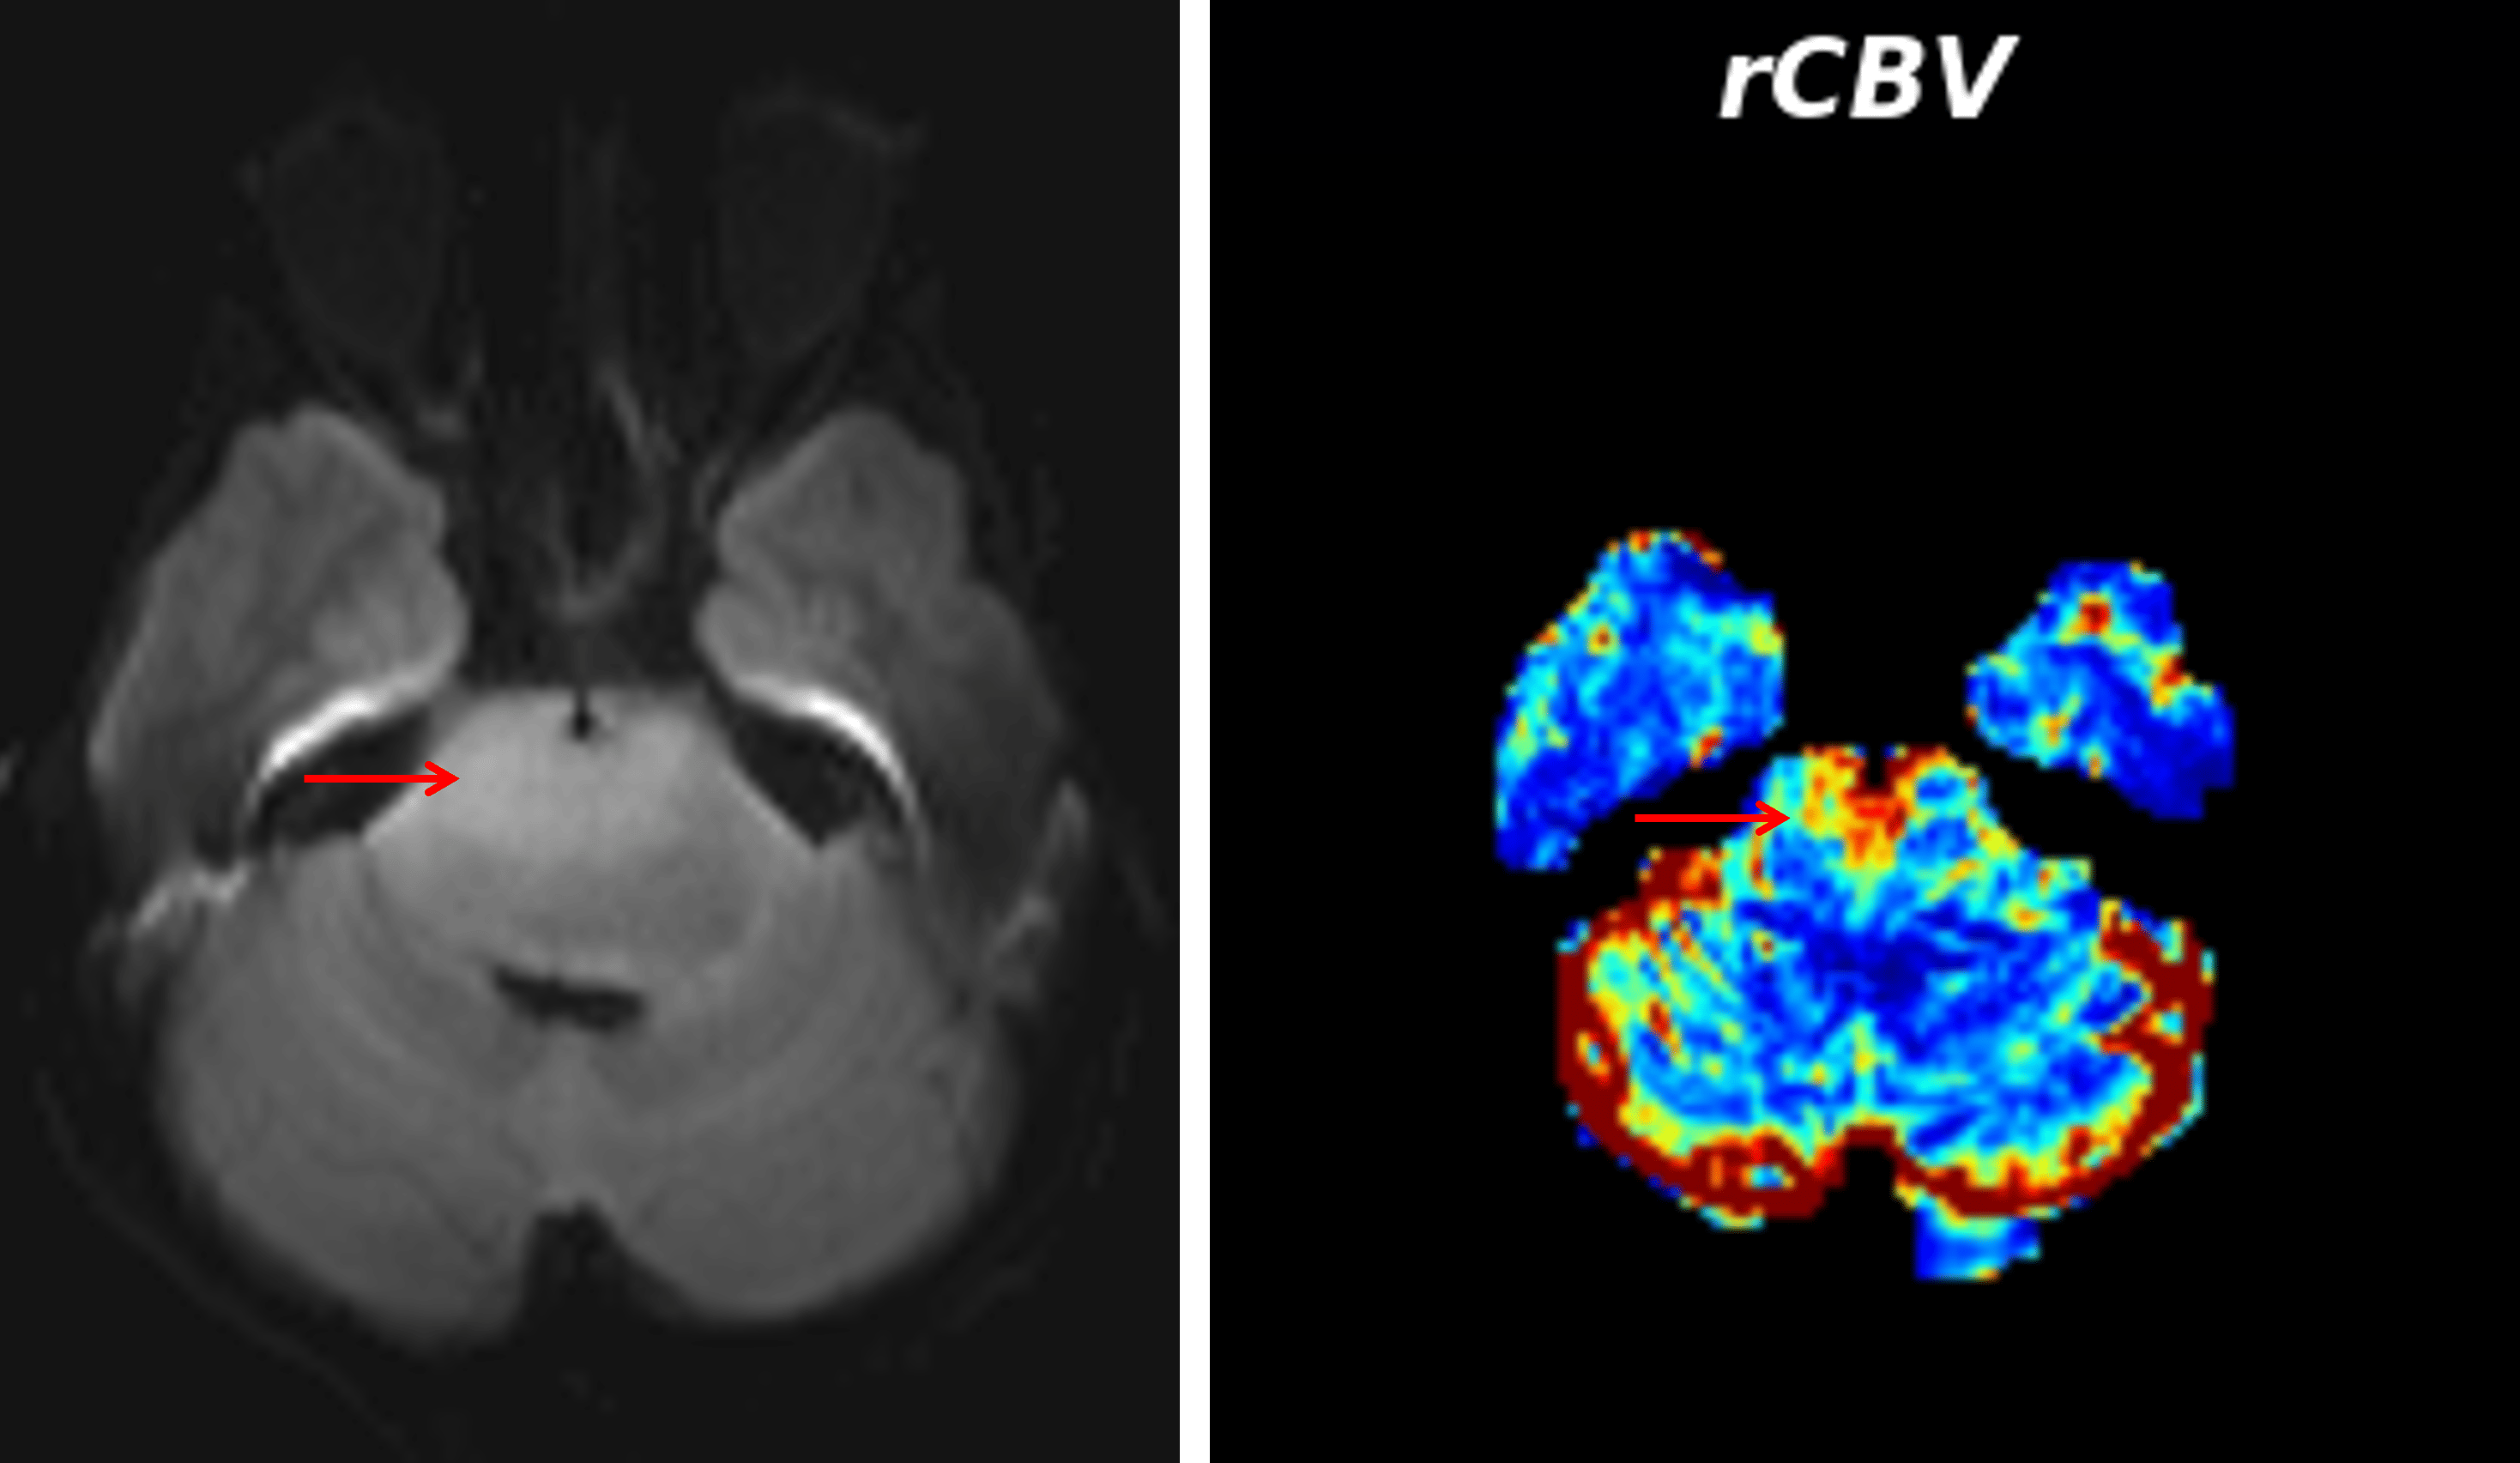

Area of mild restricted diffusion in the ventral pons, which demonstrated elevated cerebral blood volume on perfusion analysis (red arrows).